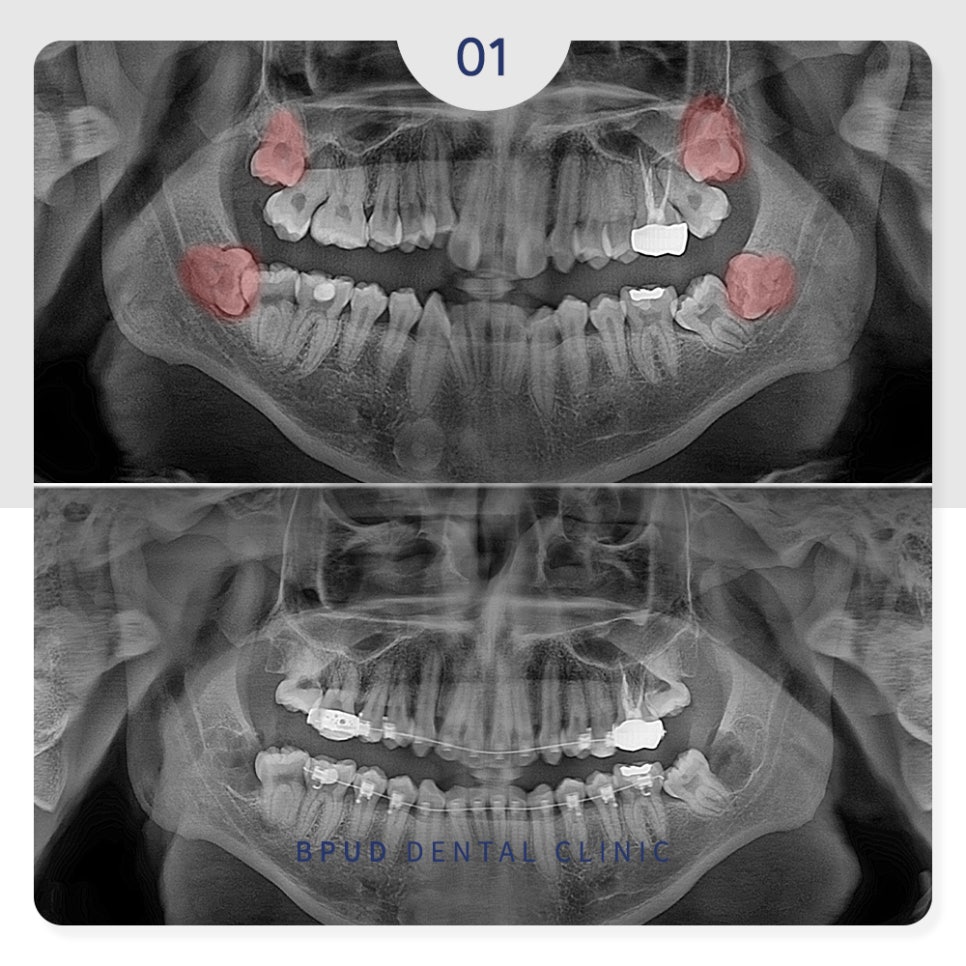

24.12.03

완전 매복 고난이도 사랑니로

신경에 완전히 닿아 있어 신경 손상의

위험이 높은 케이스였으나 문제없이

발치 계획을 수립하였습니다.

이처럼 정상적인 발치를 할 수 없는

위치에 치아가 있는 경우 발치 시

어려움이 있기 때문에

3D CT 촬영을 통해 정밀한 진단을

바탕으로 치아 상태를 입체적으로 파악하여

계획을 세워야 부작용의 위험을 줄일 수 있습니다.

양쪽의 사랑니를 모두 쪼개어

발치를 한 모습입니다.